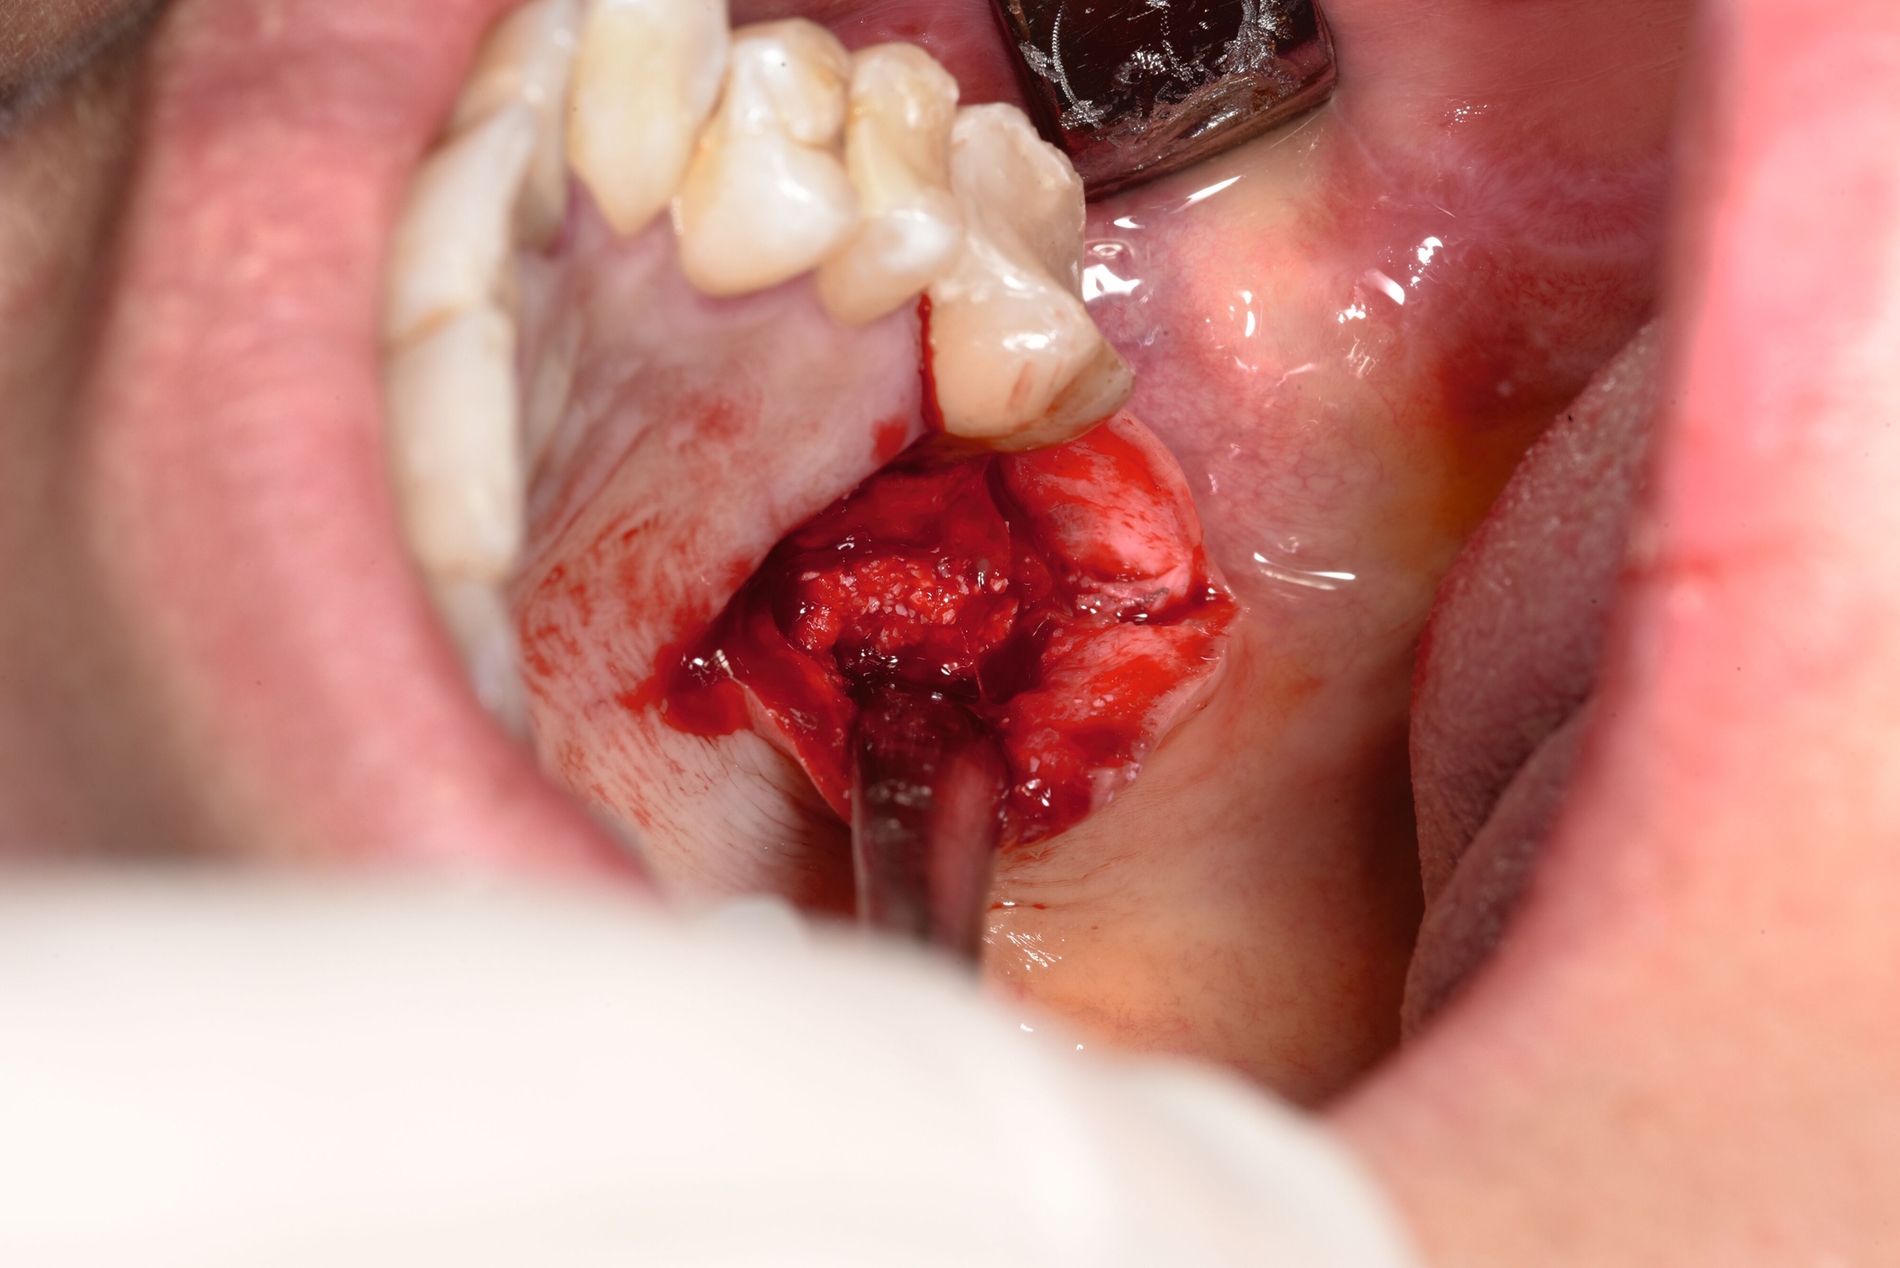

Die Schnittführung erfolgte krestal mit einer palatinalen Entlastung (Abbildung 5). Anschließend wurde der knöcherne Zugang zur Kieferhöhle unter kontinuierlicher Navigation gezielt osteotomiert (Abbildung 6). Das Navigationssystem ermöglichte dabei eine präzise Lokalisation des Fremdkörpers und erhöhte die Sicherheit in Bezug auf die angrenzenden Strukturen. Nach vorsichtiger, schrittweiser Osteotomie unter Navigationskontrolle (Abbildung 7) konnte das frakturierte Wurzelkanalinstrument schließlich sicher dargestellt und entfernt werden (Abbildung 8). Zur Auffüllung des entstandenen Defekts wurde ein mit PRF (Mectron®-Verfahren) getränktes Knochenersatzmaterial (Bio-Oss Collagen®, Geistlich®) eingebracht (Abbildung 9). Der Wundverschluss erfolgte spannungsfrei mittels Seidennaht 3-0 (Abbildung 10).